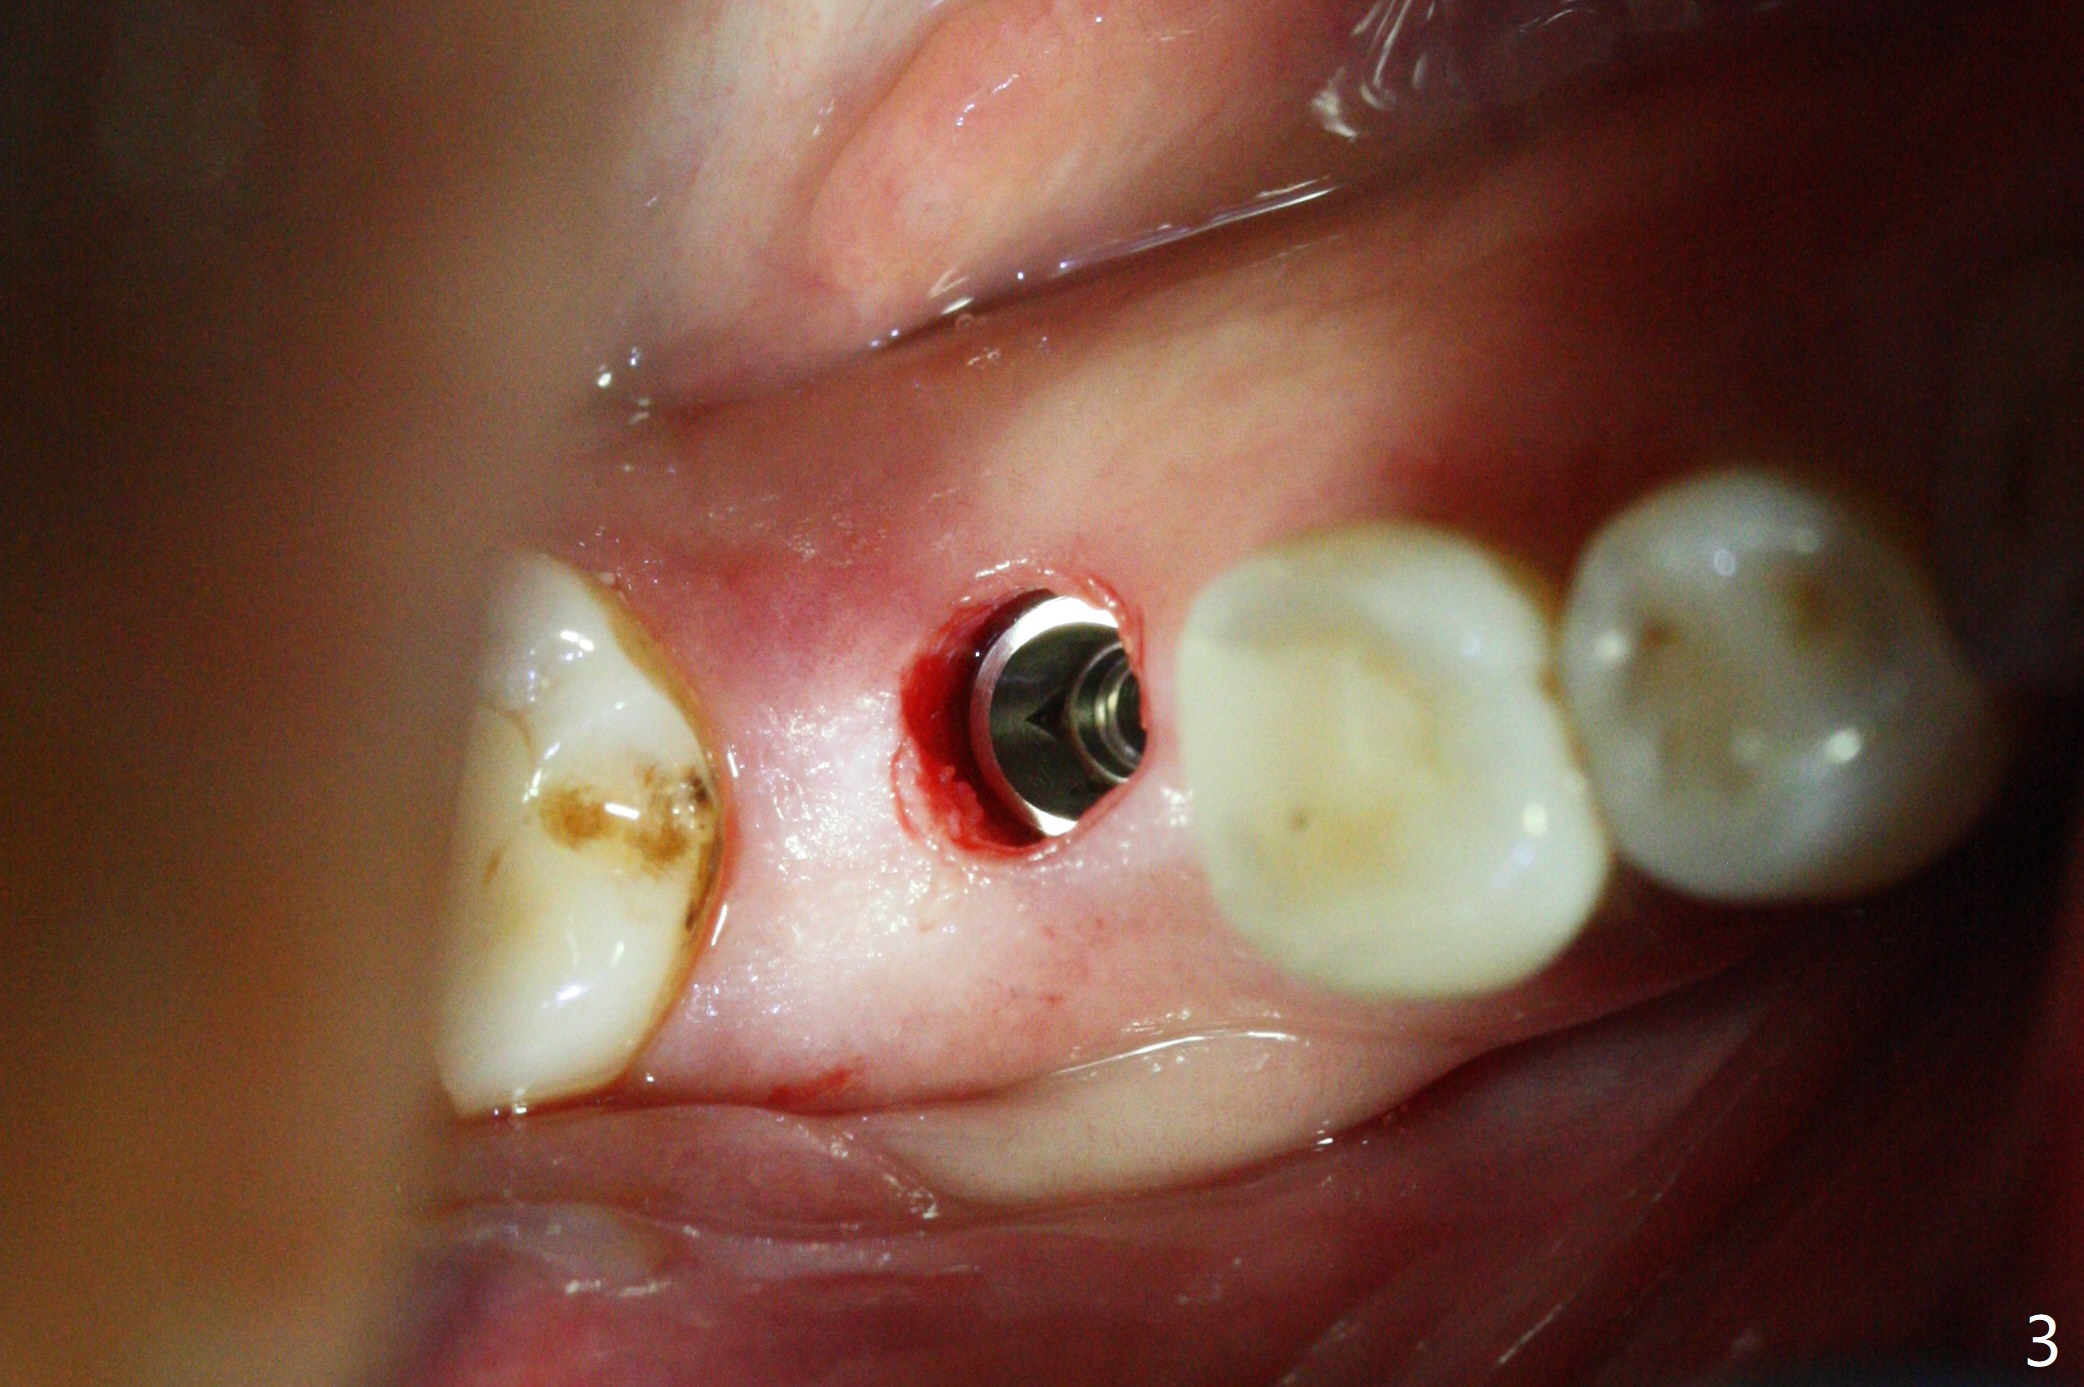

A 5x10 mm implant is placed at #30 with a surgical guide (Fig.1 *) in 10 minutes. The most amazing part of this surgery is that the guide allows you to place the implant at the precise level care-free (~ 1 mm subcrestal, Fig.2,3). Everything happens so quick that when a 5.5x3 mm healing abutment is placed (Fig.4), you are pleased to feel that the implant is stable (Fig.5). You could not ask for anymore. The fearful patient reports no postop pain. The implant is placed as planned (Fig.6, overlap image provided by the guide designer, Jennifer). The patient returns for impression nearly 2 months postop (Fig.7,8). It appears that the implant has osteointegrated without bone loss (Fig.7). The soft tissue is healthy around the just placed cementation abutment (Fig.8 (5.2x4(2) mm)). When the permanent crown is seated initially 2.5 months postop, the mesial contact is slightly tight and the occlusion is high. Bitewing shows the distal open margin (Fig.9 >). After mesial contact adjustment, the patient feels that the occlusion is better. With further occlusal adjustment, the crown is cemented without distal open margin (Fig.10). The patient returns to her home country for 3 months. The implant is doing well 3.5 months post cementation; impression is taken for #14 surgical guide.